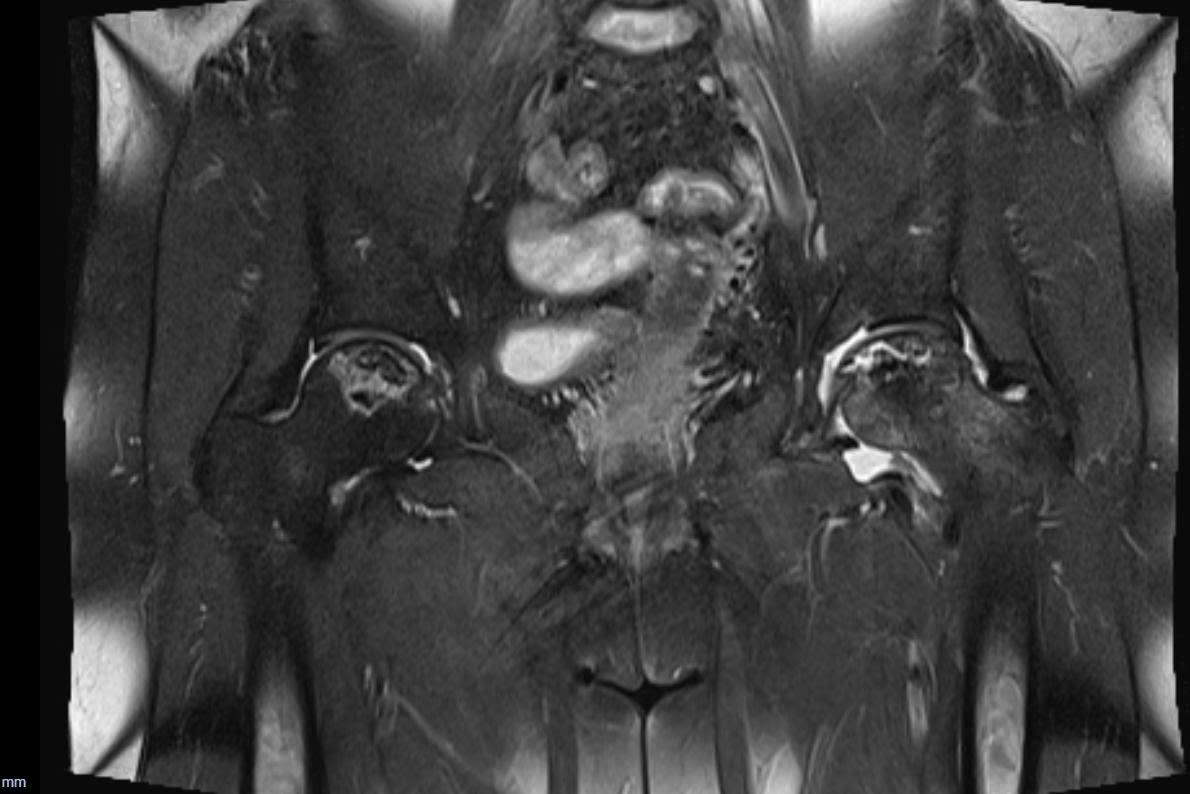

Thăm khám chuyên sâu và chụp MRI - bước ngoặt trong điều trị

Tại AIH, Bác sĩ CKII Nguyễn Viết Thịnh - Phó Khoa Ngoại Tổng quát tại Bệnh viện Quốc tế Mỹ (AIH) thăm khám lâm sàng kỹ lưỡng và xem xét lại toàn bộ phim X-quang trước đó. Dù hình ảnh X-quang không cho thấy tổn thương rõ ràng, dựa trên triệu chứng lâm sàng và diễn tiến bệnh, bác sĩ nghi bệnh nhân mắc hoại tử vô mạch chỏm xương đùi. Đây là một bệnh lý thường khó phát hiện ở giai đoạn sớm nếu chỉ dựa vào X-quang thông thường.

Sau đó, bệnh nhân được chỉ định chụp MRI khớp háng. Kết quả cho thấy tình trạng hoại tử chỏm xương đùi xuất hiện ở cả hai bên, với mức độ tổn thương rõ rệt, xác định bệnh đã tiến triển đến giai đoạn nặng, không còn phù hợp với các phương pháp điều trị bảo tồn, từ đó làm cơ sở cho quyết định can thiệp phẫu thuật thay khớp háng.

BS.CKII Nguyễn Viết Thịnh cho biết: “Hoại tử vô mạch chỏm xương đùi thường tiến triển âm thầm và dễ bỏ sót ở giai đoạn đầu nếu chỉ dựa vào X-quang hoặc thăm khám lâm sàng chưa đầy đủ. Nếu bệnh nhân được chẩn đoán sớm hơn bằng MRI, nhiều trường hợp có thể áp dụng các phương pháp điều trị bảo tồn hoặc can thiệp ít xâm lấn, giúp trì hoãn hoặc tránh phải thay khớp háng.”